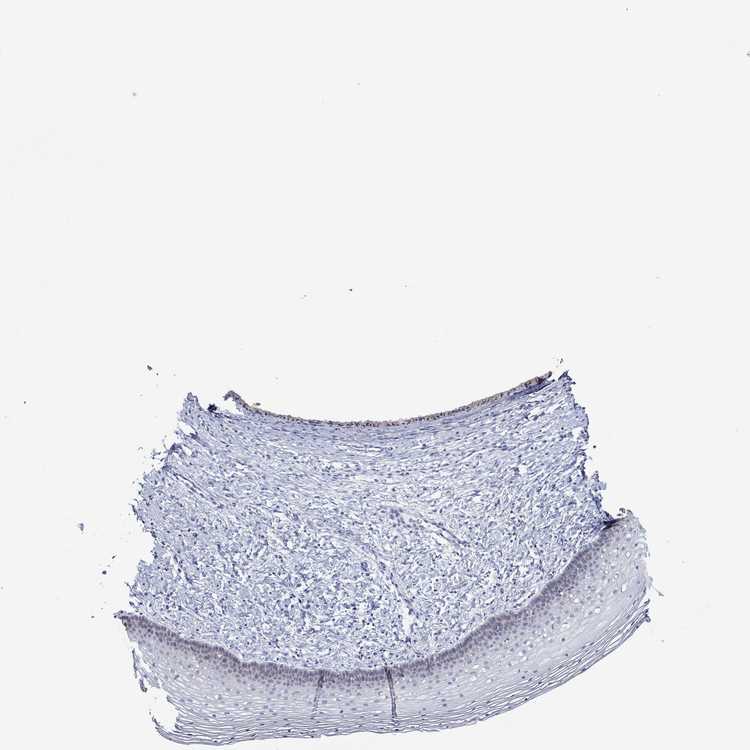

TISSUE PRIMARY DATA CERVIX Show tissue menu

Cervix

CERVIX - Expression summary

CERVIX - Antibody stainingi

Antibody staining in the annotated cell types in the current human tissue is reported as not detected, low, medium, or high, based on conventional immunohistochemistry profiling in selected tissues. This score is based on the combination of the staining intensity and fraction of stained cells.

Each image is clickable and will lead to virtual microscopy that enables deeper exploration of all samples and also displays staining intensity scores, fraction scores and subcellular localization as well as patient and tissue information for each sample.

Antibody HPA067508Antibody CAB080514Antibody CAB080517

Glandular cells Not detectedNot detectedNot detected

Squamous epithelial cells Not detectedNot detectedNot detected